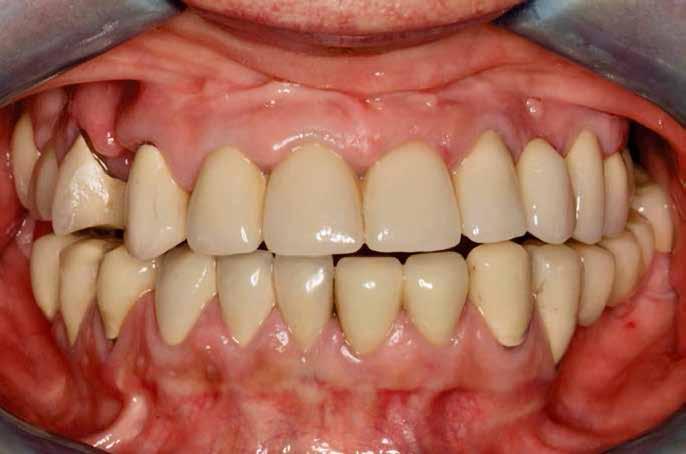

Kiindulási helyzet

A páciens egy 56 éves nőbeteg, nem dohányzik, általános egészségi állapota jó (ASA I), gyógyszert nem szed, ismert allergiája nincs. Fő panasza, amellyel klinikánkat felkereste, hogy elégedetlen mosolyával. Elmondása alapján az utóbbi években krónikus gyulladás alakult ki frontfogai körül, amely érezhető mobilitáshoz vezetett. Ez a probléma jelentősen befolyásolta a magabiztos beszédben és étkezésben. A páciens hosszú távú megoldást keresett, de aggódott a kezelések alatt fellépő esetleges fájdalom miatt. Az extraorális vizsgálat során megállapítottuk, hogy a mosolyvonal közepesen magas és a frontfogak torlódottak (1–2. ábrák). A szájüregi vizsgálat során a 1.2, 2.1 és 2.2 fogak körül előrehaladott parodontális tapadásveszteséget és mobilitást találtunk (3. ábra). A CBCT (cone beam CT) felvételen látszott, hogy a 2.1 fog bukkális csontfala hiányzik (4. ábra).

1. ábra: Az extraorális vizsgálat közepesen magas mosolyvonalat mutatott.

2. ábra: A torlódott felső frontfogak.

3. ábra: Az intraorális vizsgálat során a bal felső nagymetszőnél és mindkét oldali kismetszőnél parodontális tapadásvesztést és mobilitást találtunk.

Kezelési eredmények

A végleges lenyomatvétellel egy időben kontrollröntgeneket készítettünk az implantátumokról, hogy pontosan felmérhessük azok pozícióját és a környező szövetekhez való viszonyát (15. ábra). Hat évvel a kezelés befejezését követően a hosszú távú stabilitás és a szövetek egészségének ellenőrzésére utánkövetéses röntgenek készültek (16. ábra). A hat- (17–18. ábrák) és a kilencéves (19. ábra) utánkövetés során az átfogó klinikai és röntgenvizsgálatok kedvező eredményeket mutattak az osszeointegráció, az implantátumok körüli csontsűrűség és az esztétika terén is. Ezen eredmények együttesen a kezelés hosszú távú sikerét jelezték. A kezelés a kemény- és a lágyszövetek esetében is rendkívül egészséges állapotot eredményezett. A páciens nagyon hálás volt, hogy a kezelés minden apró részletére gondosan ügyeltünk.

A fenntartó kezelés hatékonysága alapvető az elért eredmények hosszú távú megőrzésében. A páciens elmondása alapján ismét képes volt megfelelően rágni és magabiztosan beszélni. Az átfogó kezelés sikerét az is bizonyítja, hogy megvalósult a páciens „álommosolya”.

12. ábra: A hét hónapos kontroll alkalmával sikeres lágyszöveti gyógyulás látható. – 13. ábra: A végleges fogpótlás. – 14. ábra: A végleges koronák megjelenése esztétikus. – 15. ábra: A végleges lenyomatvételkor készült kontrollröntgenek igazolják az implantátumok pontos pozícióját és a környező csont épségét. – 16. ábra: Az utánkövetéses röntgenvizsgálatok során értékeltük az implantátumok körüli szövetek hosszú távú stabilitását és épségét. – 17. ábra: A hatéves kontrollnál kedvező esztétikai eredmény látható. – 18. ábra: A hatéves kontrollnál kielégítő klinikai eredmény látható. – 19. ábra: A kilencéves kontroll alkalmával látható, hogy a kemény- és lágyszövetek egészsége megtartott.